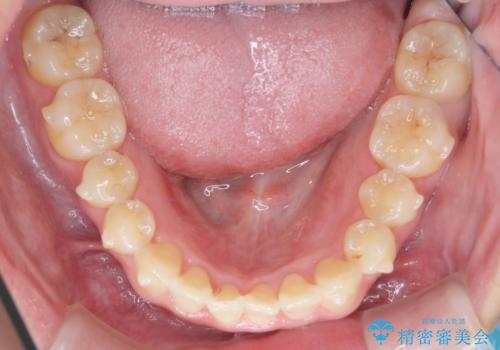

- 前歯のねじれを改善したい、と矯正治療を希望され来院されました。

上下の歯のがたつきを改善するマウスピース矯正治療と、下顎に見られる大きな骨隆起を外科的に除去する治療計画を進めていきます。

歯並びが改善したとともに、骨隆起を除去したことで舌をしまうスペースも増え安定した口腔内環境を確立することができました。